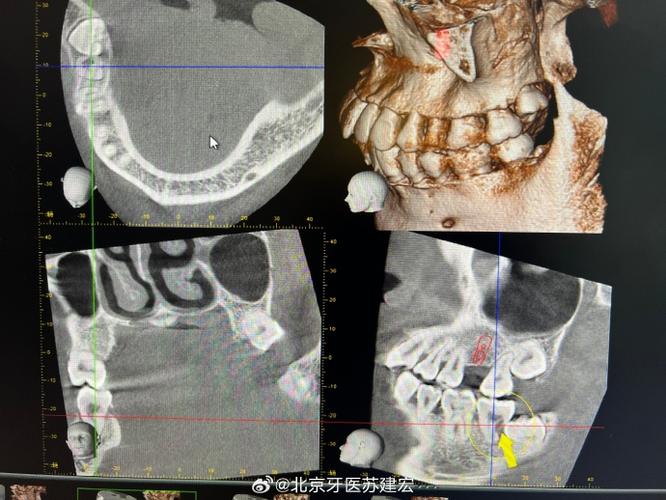

(图片来源网络,侵删)

- 图像后处理:

- 操作技师或医生需熟练使用工作站软件进行多平面重组、曲面重组、三维表面重建、最大密度投影、仿真内窥镜等操作。

- 重点观察:

- 牙齿数量、形态、位置、萌出情况。

- 牙根形态、弯曲、位置、长度、有无吸收、根分叉情况。

- 颌骨(上颌、下颌)的形态、大小、密度、有无病变(囊肿、肿瘤、骨皮质异常)。

- 牙槽骨高度、厚度、形态(尤其需要拔牙的部位)。

- 上颌窦、鼻腔、下颌管、颏孔等重要解剖结构的位置和关系。

- 颞下颌关节(髁突、关节窝、关节间隙)的形态、位置、骨质情况(在需要时)。

- 咬合关系(三维评估)。